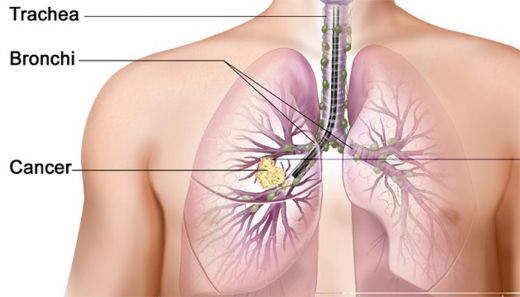

Akciğer Kanseri Metastaz Belirtileri ve Tedavisi Akciğer kanseri, dünya genelinde en sık görülen ve en ölümcül kanser türlerinden biri olup, genellikle erken evrelerinde belirgin semptomlar göstermemektedir. Ancak hastalık ilerledikçe, metastaz (kanserin vücudun diğer bölgelerine yayılması) belirtileri ortaya çıkmaktadır. Bu makalede, akciğer kanseri metastazının belirtileri ve tedavi yöntemleri detaylı bir şekilde ele alınacaktır. Akciğer Kanseri Metastaz Belirtileri Metastaz, akciğer kanserinin ilerlemesi ile birlikte farklı organlara ve dokulara yayılması anlamına gelir. Bu süreçte gözlemlenen bazı belirtiler şunlardır:

Metastazın Yayılma Alanları Akciğer kanseri, vücudun farklı bölgelerine metastaz yapabilir. Bu alanlar arasında: